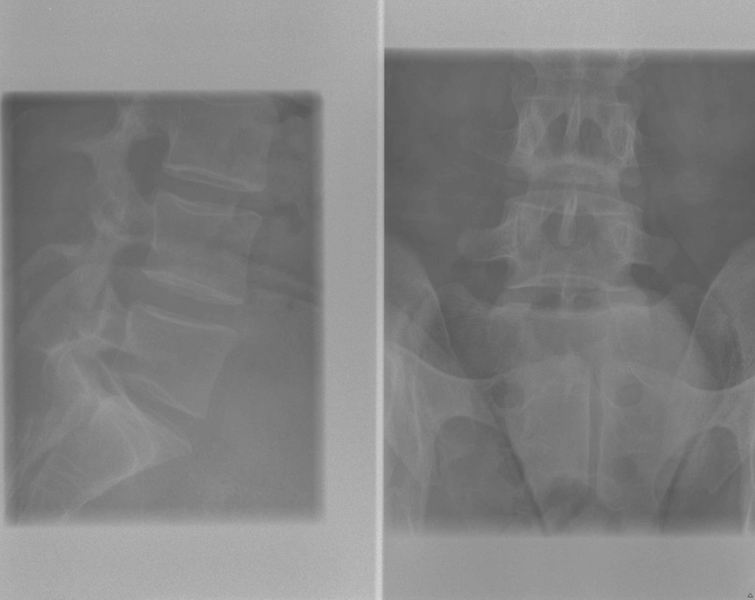

Dorsale wervelzuil